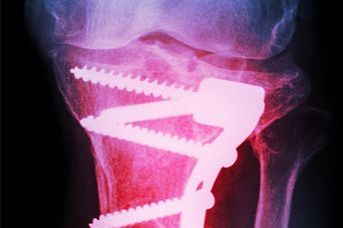

Wir bieten einte optimale und individuelle Therapie bei allen Verletzungen und ein umfangreiches Spektrum an unfallchirurgischen Operationen an. Die Klinik versorgt ambulant und stationär Arbeitsunfälle.

Es sind alle Möglichkeiten der bildgebenden Diagnostik wie Sonografie, CT, MRT und Angiografie sowie der interventionellen Therapie am Standort vorhanden.